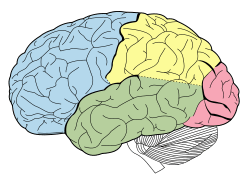

Principal fissures and lobes of the cerebrum viewed laterally. (Frontal lobe is shown in blue.) | |

The frontal lobe, located at the front of the brain, is one of the four major lobes of the cerebral cortex in the mammalian brain. The frontal lobe is located at the front of each cerebral hemisphere and positioned in front of the parietal lobe and above and in front of the temporal lobe. It is separated from the parietal lobe by a space between tissues called the central sulcus, and from the temporal lobe by a deep fold called the lateral sulcus also called the Sylvian fissure. The precentral gyrus, forming the posterior border of the frontal lobe, contains the primary motor cortex, which controls voluntary movements of specific body parts.

On the lateral surface of the human brain, the central sulcus separates the frontal lobe from the parietal lobe. The lateral sulcus separates the frontal lobe from the temporal lobe.